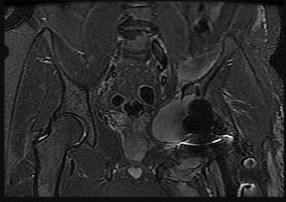

Figures 6a through 6d are the radiographs and T1-weighted sagittal and fat-saturated axial MR images of an otherwise healthy 56-year-old man who has anterior knee pain and intermittent swelling after sustaining a noncontact twisting injury. Low-power and high-power hematoxylin and eosin stained histologic specimens are shown in Figures 6e and 6f. Based on the history, radiographs, CT scan, MR imaging, and histologic findings, what is the most likely diagnosis?

The lesion in the posterior intercondylar knee notch is a benign synovial hemangioma. Intralesional calcifications, classically associated with hemangiomas, are frequently not identified on plain radiographs. The MR imaging reveals a hypervascular lesion with multiple filling defects, with hyperintensity on T2-weighted images and low-to-intermediate signal intensity on T1-weighted images. Histologically, vascular lakes within fine capillaries with a synovium on the surface of the lesion are characteristic of this condition. Many patients with synovial hemangioma have pain, swelling, stiffness, or mechanical symptoms. The correlation of symptoms with the hemangioma for this patient is unclear because there was recent trauma and a concurrent meniscus tear. Simultaneous treatment of both potential sources of pain is typically recommended. As with PVNS, the disease can be localized or diffuse. Surgical excision, either open or arthroscopic, is the recommended treatment. PVNS is the most common intra-articular tumor, but hypointensity in either the diffuse or localized type is characteristic in both T1- and T2-weighted images. Synovial sarcoma, although often found close to a joint, is not characteristically found within a joint.